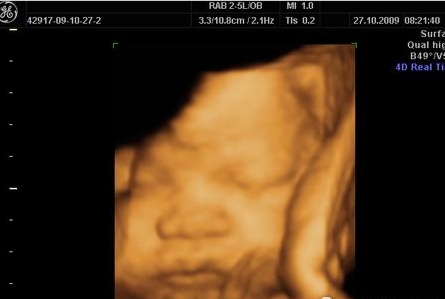

四维彩超:

过去的B超设备只能检查胎儿的生理指标,而四维彩超还能对胎儿的体表进行检查,如唇裂,脊柱裂,大脑、肾、心脏、骨骼发育不良等,以便尽早的进行治疗。生个聪明健康的小宝宝,并且将宝宝的样子和动作制作成照片或DVD,让宝宝拥有最完整的0岁相册,这已经不再是幻想。

广告中“四维彩超”的彩超,也是“伪彩超”。医学上彩超只有两个颜色:红和蓝。代表静脉血和动脉血的不同流向。但我们所熟悉的胎儿“四维彩超”却是橘色。目的只是为了让胎儿的“照片”更加柔和、清晰。